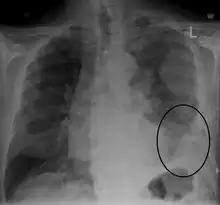

Imaging

Diagnosing mesothelioma is often difficult because the symptoms are similar to those of a number of other conditions. Diagnosis begins with a review of the patient's medical history. A history of exposure to asbestos may increase clinical suspicion for mesothelioma. A physical examination is performed, followed by chest X-ray and often lung function tests. The X-ray may reveal pleural thickening commonly seen after asbestos exposure and increases suspicion of mesothelioma.[14] A CT (or CAT) scan or an MRI is usually performed. If a large amount of fluid is present, abnormal cells may be detected by cytopathology if this fluid is aspirated with a syringe.[10] For pleural fluid, this is done by thoracentesis or tube thoracostomy (chest tube); for ascites, with paracentesis or ascitic drain; and for pericardial effusion with pericardiocentesis. While absence of malignant cells on cytology does not completely exclude mesothelioma, it makes it much more unlikely, especially if an alternative diagnosis can be made (e.g., tuberculosis, heart failure). However, with primary pericardial mesothelioma, pericardial fluid may not contain malignant cells and a tissue biopsy is more useful in diagnosis.[10] Using conventional cytology diagnosis of malignant mesothelioma is difficult, but immunohistochemistry has greatly enhanced the accuracy of cytology.